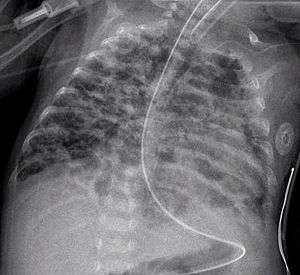

A chest radiograph showing bronchopulmonary dysplasia.